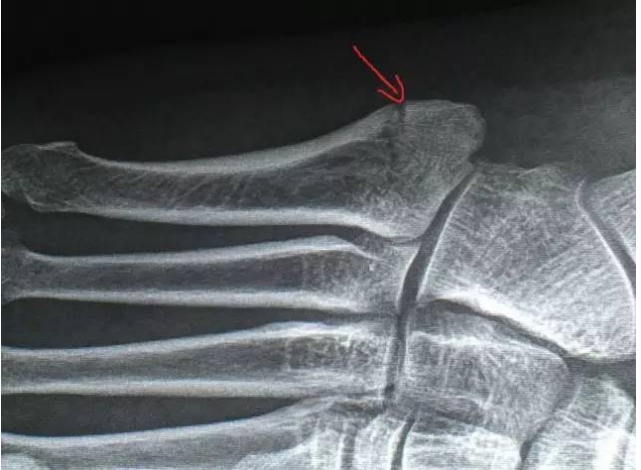

2016年9月22日,励建安教授在晨跑时右脚外侧扭伤,第五跖骨基底部发生骨折。

第19天,X光片复查,骨折没有移位,骨折线模糊。